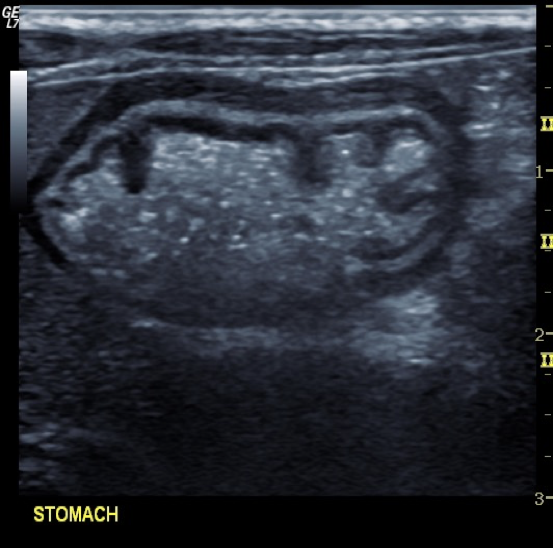

Magnified view of normal gastric wall layer architecture

Normal fluid gastic content – prominent luminal invaginations represent rugal folds